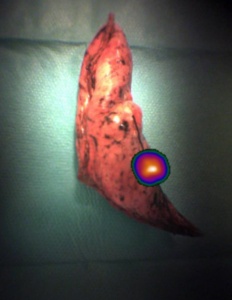

Acto quirurgico. A la derecha, imagen tomada con gammacámara portátil de la pieza quirúrgica de segmentectomía S1 del LSD, que confirma la presencia del radiofármaco depositado en el nódulo pulmonar.